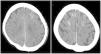

The first recommended test, after a detailed neurological examination, is usually a brain CT without contrast, which could show brain edema plus enhancement of cortical or subarachnoid space of the affected areas,22 although it may occur that radiological signs are absent.20 Particularly the dual energy CT allows to differentiate whether the observed hyperdensities correspond to contrast or hemorrhage.12 The reported cases of patients on HD do not present different radiological signs (Fig. 1). Another useful test is MRI, which is able to demonstrate ischemic lesions, mainly with the DWI sequence through the restriction in diffusion produced by ischemia; the FLAIR sequence identifies the edematous areas22 (Fig. 2). Another test that helps to differentiate, especially from subarachnoid hemorrhage, is the analysis of cerebrospinal fluid (CSF), where the absence of xanthochromia or red blood cells would argue against hemorrhage. Additionally, a higher concentration of contrast in CFS than blood would strongly suggest contrast extravasation.4

Brain computed tomography (CT) scan without contrast of a 63-year-old woman on hemodialysis undergoing third endovascular embolization of an intact anterior communicating artery aneurysm with postprocedural left hemiparesis (having undergone two previous uneventful interventions in the past). CT scan shows cortical hyperdensity in the sulcus of both frontal lobes. Matsubara et al.3 With permission of the authors.